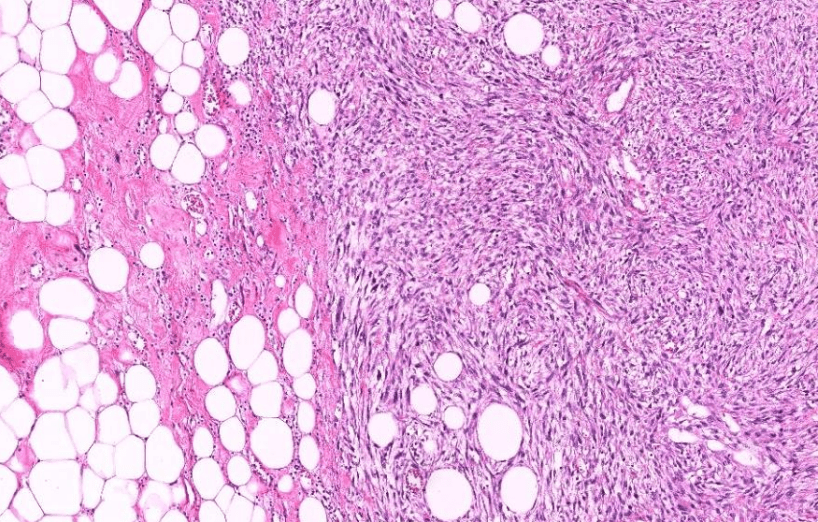

lung adenocarcinoma

colon cancer

endometrial cancer